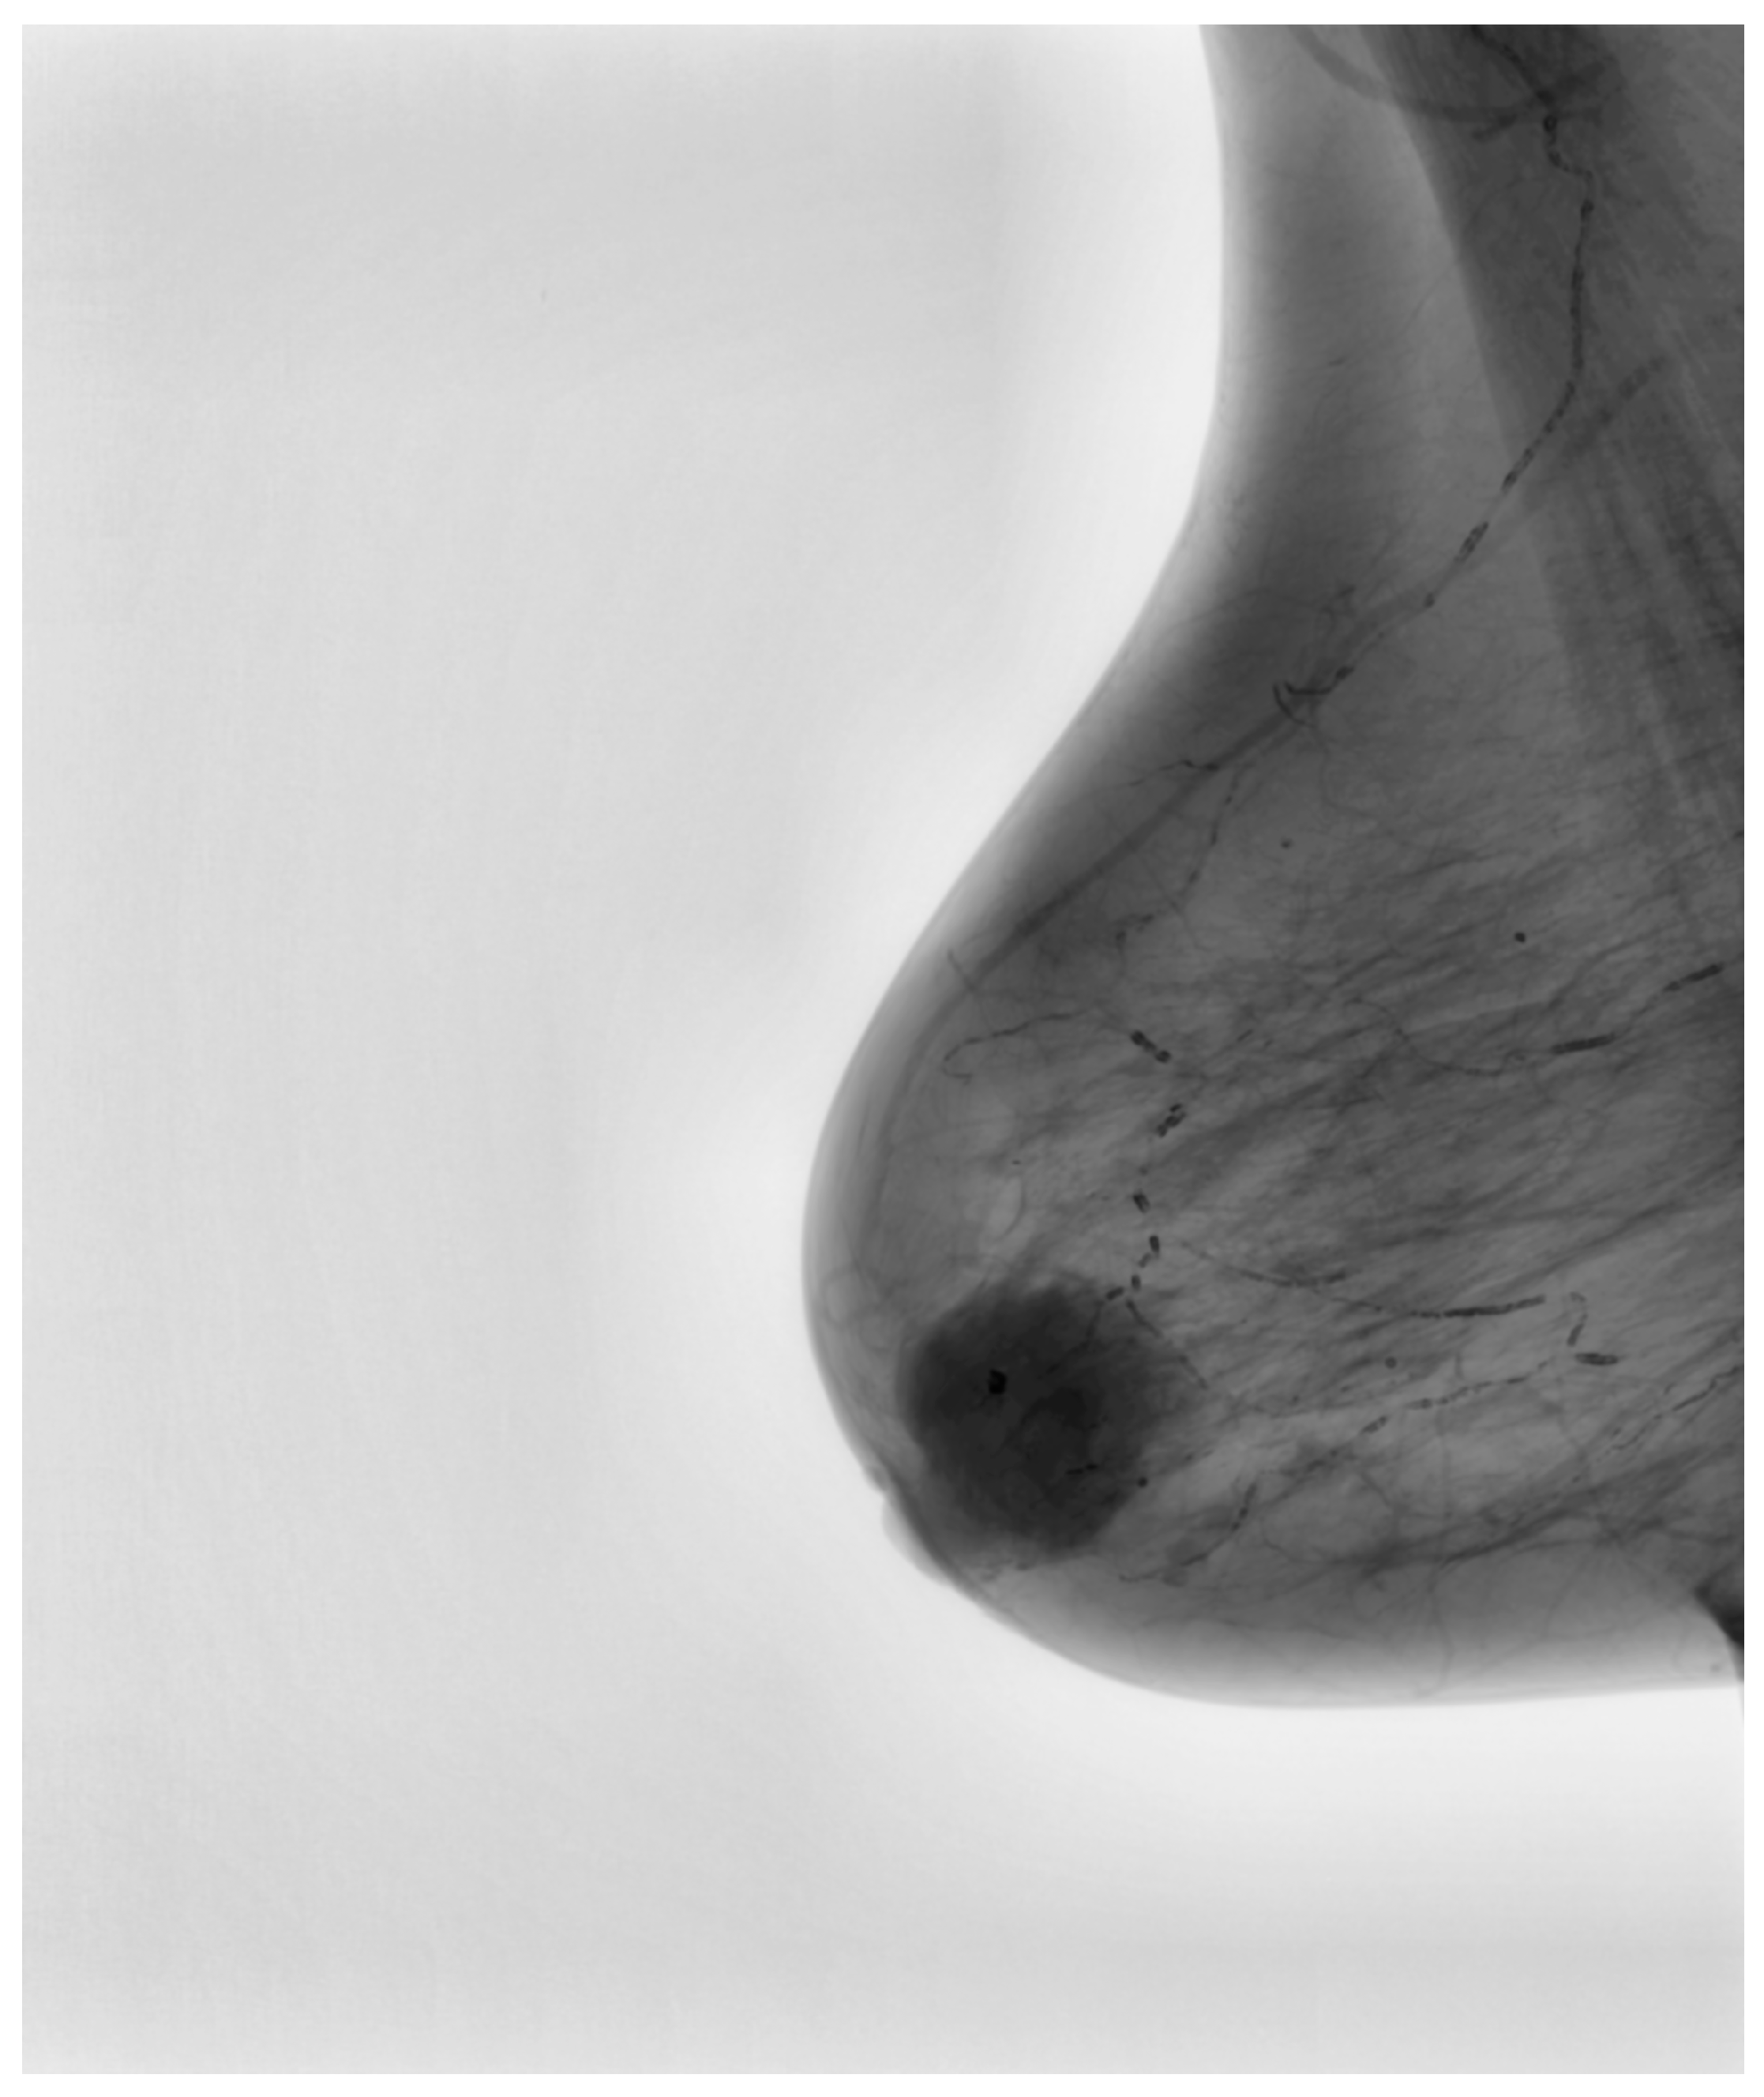

Following this conversion, a series of image enhancement techniques were applied to optimize the quality of mammograms before they were introduced into the convolutional neural network. Given that mammographic images inherently exhibit low contrast, particularly in cases involving dense breast tissue, contrast-limited adaptive histogram equalization was employed to improve the visibility of structural variations within the breast parenchyma. This enhancement method, as depicted in Figure 3, demonstrated a substantial improvement in contrast while simultaneously preventing overamplification of noise, which could otherwise introduce false-positive findings during AI-based classification.

Figure 3.

Intermediary-processed mammographic image showcasing enhanced contrast and denoising.

In addition to contrast enhancement, noise reduction was performed using an advanced denoising algorithm to eliminate non-informative variations caused by acquisition artifacts or background irregularities. Reducing noise is particularly critical in mammographic AI applications, as unwanted fluctuations in pixel intensity can lead to the misinterpretation of tissue textures and edge structures. By carefully suppressing irrelevant noise while preserving pathologically relevant signals, the algorithm enhanced the clarity of microcalcifications, spiculations, and soft-tissue masses. The intermediary processed image, as shown in Figure 3, illustrates this refinement.